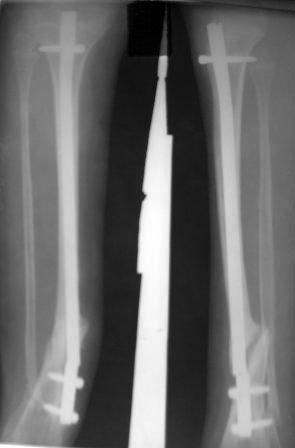

Сегодня сделал рентген, гвоздь сломался, видимо усталостный

перелом.гвоздь и сломанный часть легко удален, пока дистракционный

остеосинтез аппаратом Илизарова и будем постепенно исправить деформацию.

микрохирургия не доступно, оказалось родители и повторный БИОС не могут

из-за финансов,учитывая что ложный сустав не атрофичный и даже несколько

гипертрофичный может продолжать аппаратное лечение? Или еще какие

варианты? ,будем думать.